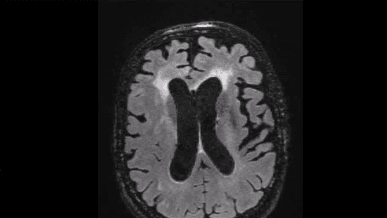

Exemplo prático de novos critérios em EM

No vídeo “Exemplo Prático de Novos Critérios em EM”, os Drs. Tomás Freddi explora os avanços recentes nos critérios diagnósticos para Esclerose Múltipla (EM). O…

Novos critérios Esclerose Múltipla – 2025

No vídeo “Novos Critérios para Esclerose Múltipla 2025”, o Dr. Tomás Freddi apresenta atualizações importantes sobre os critérios diagnósticos para a esclerose múltipla (EM), um…